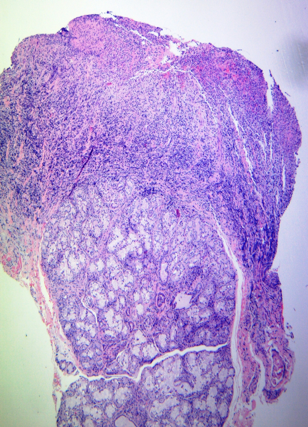

Paciente de sexo masculino de 6 años de edad, con antecedentes de insuficiencia renal crónica secundaria a síndrome nefrótico congénito tipo finlandés. Inicia tratamiento sustitutivo con diálisis peritoneal a los 5 años, el cual debe suspenderse a los dos meses por presentar una comunicación pleuroperitoneal, indicándose como terapia de sustitución renal hemodiálisis. Recibe trasplante renal 4 meses después, de donante cadavérico. La inmunosupresión de inducción fue basiliximab y pulsos de metilprednisolona; y de mantenimiento prednisona, tacrolimus y micofenolato mofetil. Serología VEB pre trasplante negativa. A los 3 meses del trasplante, presenta cuadro de odinofagia y fiebre intermitente, asociado a úlceras orales dolorosas (Figura 1) y adenopatías submaxilares. Las PCR seriadas para VEB, HHV-6 y CMV se mantuvieron indetectables, sin ascenso de carga viral previo a la manifestación clínica. Se reduce micofenolato al 50% y se cambia aciclovir por valganciclovir, sin mejoría clínica. El paciente es internado por persistencia de fiebre, lesiones bucales con mal manejo del dolor y pérdida de peso. Se realiza ecografía abdominal que evidencia esplenomegalia; hemocultivos, urocultivo y cultivo faríngeo que resultan negativos, al igual que las cargas virales para CMV y VEB. Hisopado de lesiones bucales con resultado positivo para VEB y HHV-6. Biopsia de lesión ulcerada informa infiltrado linfocitario de inmunofenotipo predominante T mixto (CD4 y CD8 positivo), difuso en corion y con exocitosis marcada, a favor de proceso inflamatorio reactivo (Figura 2). La lesión no fue clasificada como PTLD ya que no reunía los criterios según la clasificación de la OMS, informándose compatible con un proceso inflamatorio reactivo, sin evidencia de PTLD. La detección de VEB se realizó por hibridación in situ (EBER-ISH) e inmunohistoquímica para LMP1, ambas con resultado negativo. Y la de HHV-6 se realizó por PCR en muestra de hisopado de lesiones orales. Se continúa tratamiento con ganciclovir obteniéndose mejoría de las lesiones al cuarto día de su inicio. Se disminuye inmunosupresión con dosajes de tacrolimus entre 6-8 ng/ml, se suspende micofenolato, se aumenta prednisona a 10 mg y se realiza una dosis de gammaglobulina EV 500 mg/kg. Por buena evolución clínica a los 14 días se secuencia terapia a vía oral con valganciclovir, completando 21 días totales, con resolución completa de las lesiones. Durante el seguimiento no se evidenció seroconversión para VEB.

Figura 2. Hematoxilina-Eosina (5X). Imagen panorámica de la lesión ulcerada, con infiltrado inflamatorio denso en la mucosa y submucosa